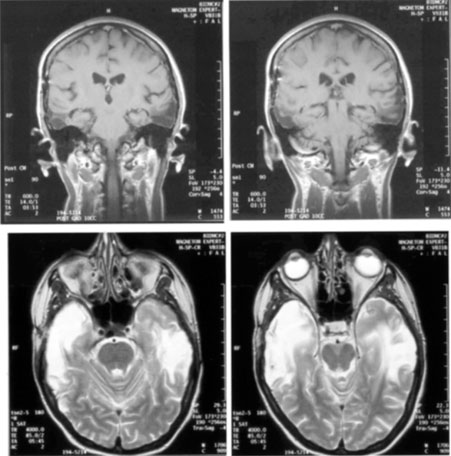

Fig. 15. Bilateral incomplete hemianopia. A 69-year-old man with decreased vision after prostate surgery. A. Fields show remaining central parafoveal vision with some sparing of inferior left quadrant. Note how the defect respects the vertical meridian. B. MRI shows bilateral medial occipital infarction, with sparing of the occipital poles, accounting for the macular-sparing bilaterally. (Courtesy of Dr. Lucia Vaina.)

Cerebral Blindness